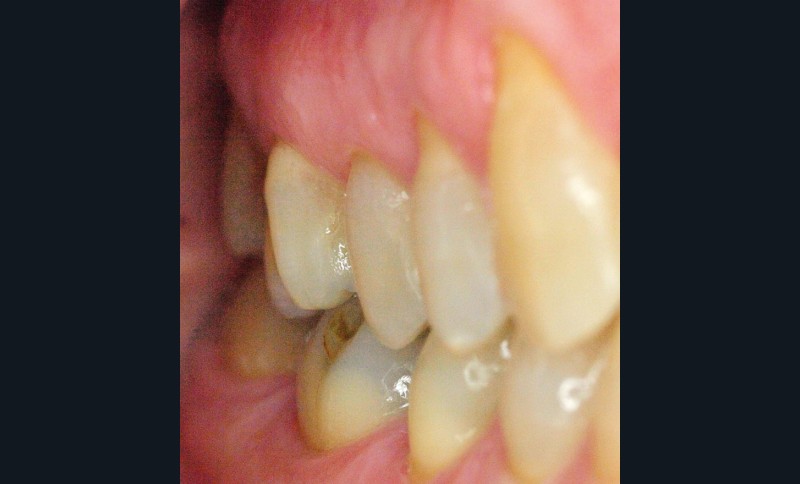

Voilà 6 mois, une patiente se présente à notre cabinet au motif d’une douleur récurrente sur le secteur molaire supérieur droit lors de la mastication. Une anamnèse rapide et cadrée est réalisée pour optimiser le temps passé et avancer les éléments diagnostiques. La patiente décrit une gêne ancienne, déclenchée essentiellement par la mastication. À l’auscultation, les examens endo-buccaux et radiologiques montrent une denture superbe avec très peu de soins, une hygiène buccale sans reproche, et des fonctions manducatrices saines [1] (fig. 1 et 2).